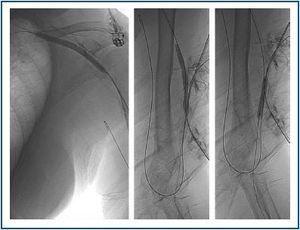

First, using ultrasound monitorisation, the access is threaded in the opposite direction from the arterial anastomosis. A guide wire and catheter is used to clear the obstructed segment to connect with the venous area free from thrombus. For PTFE grafts, this area is generally distal to the venous anastomosis. A safety wire is placed and we begin to aspirate thrombi with a large 7 to 9 French catheter (figures 1 and 2). Once the segment is free from thrombi, the catheter is threaded toward the arterial anastomosis and the same operation is repeated. When the access is free from thrombi, we inflate the underlying stenotic areas responsible for the thrombosis with an angioplasty balloon (figures 3 and 4). Medication during the procedure consists of midazolam as a sedative, an antibiotic (third-generation cephalosporin) and a heparin bolus with 3000-5000 IU of sodium heparin. If the patient needs dialysis immediately, the catheter introducers are left in and dialysis is performed using them. LMWH is recommended on non-dialysis days.

Figure 1.

Figure 2.

Figure 3.

Figure 4.